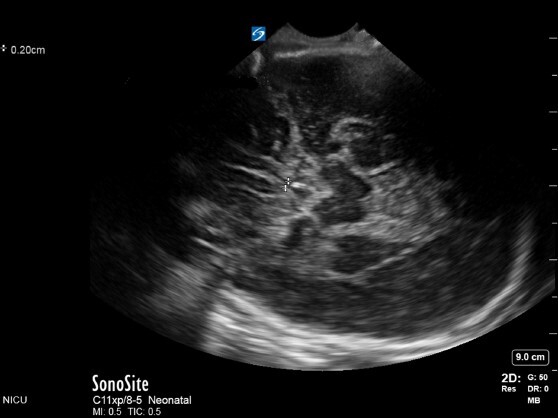

Anterior Fontanelle 3rd Ventricle Width 2 Image